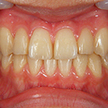

11. 術後正面

矯正装置による動的移動を終え、ブラケットを除去して歯冠研磨した後の正面写真です。ブラケット装着期間は約2ヶ月強。その間は毎週来てもらいました。もちろん早ければ良いというわけではなく、無理な歯牙移動はさまざまな弊害をもたらします。後は可徹式の保定装置を作製します。

12. 術後上顎

術前と比較して前歯の翼状捻転の改善、上顎顎堤の拡大が認められます。

当然顔貌の変化も認められ、「ちょっと下顎が過成長なのかな?」と思った顔貌も改善しました。上顎の成長が止まる時期でしたが、少し手を加えるといわゆる成長曲線の範疇に戻ることをよく経験します。